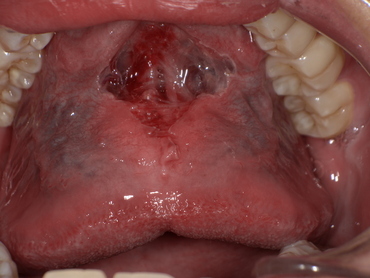

After

舌小帯形成術後、舌の動きがスムーズになり、上あごにしっかりと届くようになりました。これにより、発音に必要な舌の動きが改善されます。

成術を実施(約15分)

局所麻酔で痛みは最小限。術後は舌の動きが滑らかに。

● 術後経過

リハビリと発音練習を続けることで、約2週間後にはラ行・サ行の発音が明確になりました。

話すことへの自信を取り戻し、自然な会話ができるようになりました。